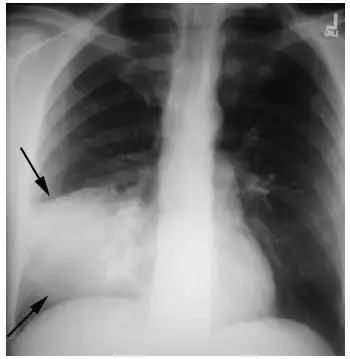

大叶性肺炎